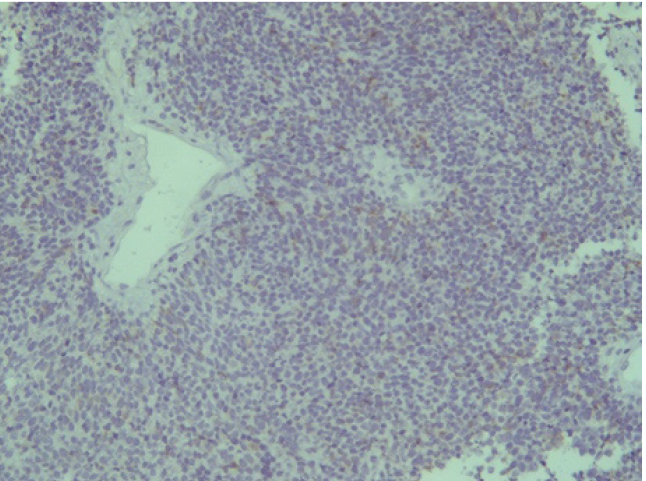

Отрицательная экспрессия была отмечена в диагностических образцах с использованием антител к Keratin.Pan, CD45, p63, S100, EMA (E29), TTF1(рис. 7–12).

Рис. 7. Keratin.Pan [AE/AE3] ×200

Рис. 8. CD 45 [Cocktail] ×200

Рис. 9. p63 [7JUL] RTU ×200

Рис. 10. S100 ×200

Эти результаты иммуногистохимического исследования подтверждают наибольшее соответствие иммунофенотипа опухоли – ольфакторной нейробластоме (G3 по Hyams) М9522/33.